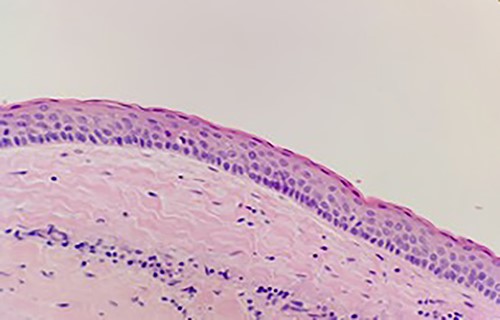

Histological assessment confirmed parakeratinized epithelium with a prominent palisaded basal layer. The findings were confirmatory for an OKC (Fig. 9). Clinical review at 6 months depicted no evidence of recurrence. A CT for further assessment is planned, with consideration of an examination under anesthetic, with the potential for pre-lacrimal stent insertion to facilitate Sino-antral washout.

Keratinizing squamous epithelium with prominent basal palisading (H&E stain, 400× magnification).

Histologically, the subtypes of OKC have been divided into parakeratinized and orthokeratotic. The parakeratotic subtype is the most frequent (80%) and is significantly more aggressive than its counterpart, with a high propensity for recurrence [8]. Those associated with Gorlin–Galtz syndrome are likely to have multiple cysts, dental, skeletal, neurological and ophthalmic abnormalities and a higher rate of recurrence. Our patient did not exhibit any of said features and did not warrant further investigation.